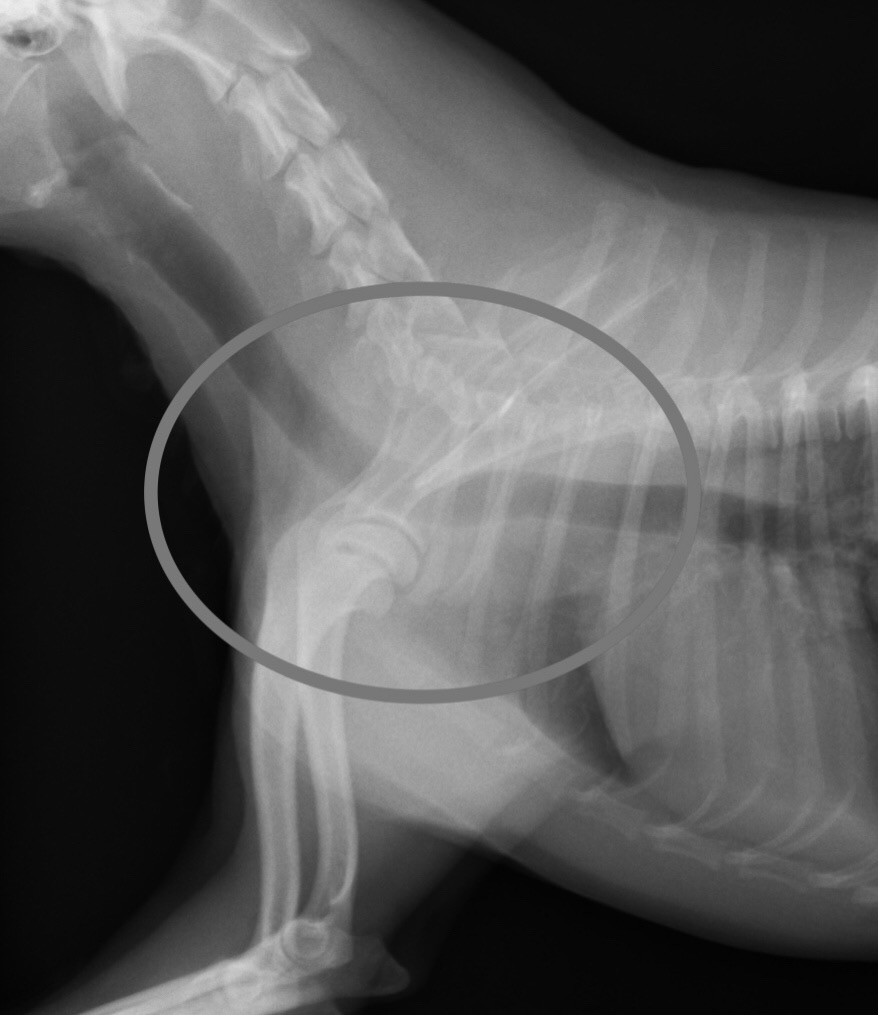

手術後1ヶ月のレントゲン画像。 1と比べて、しっかりと拡張した頸部気管が観察されます。 臨床症状も1ヶ月時点でほぼ全て消失しました。